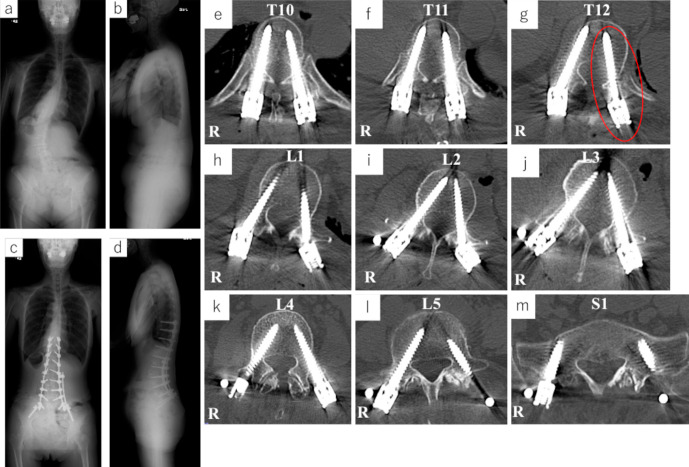

Spinal Subarachnoid Hemorrhage as a Very Rare Complication Following Circumferential Minimally Invasive Surgery Using Lateral Interbody Fusion and Percutaneous Pedicle Screw Fixation for Adult Spinal Deformity.

经皮椎弓根螺钉经外侧椎体间融合术治疗成人脊柱畸形后,椎蛛网膜下腔出血是非常罕见的并发症。